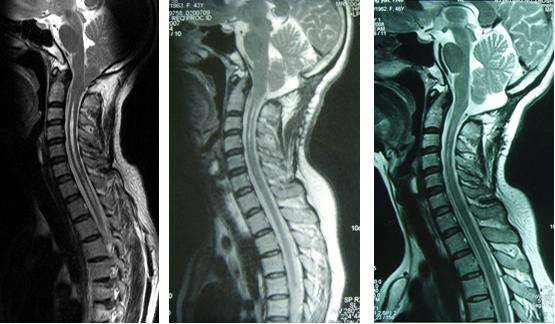

病例二:李某,女,45岁,双侧上肢麻木5年,右上肢为重。

术前;术后3个月,空洞缩小;术后1年,空洞消失

结论:后颅窝减压-枕大池成型术是治疗小脑扁桃体下疝脊髓空洞症的有效方式。